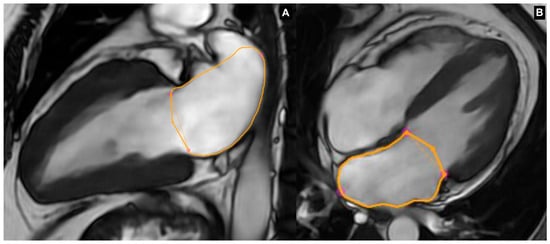

3.2.1. Left Atrial Volume and Morphology